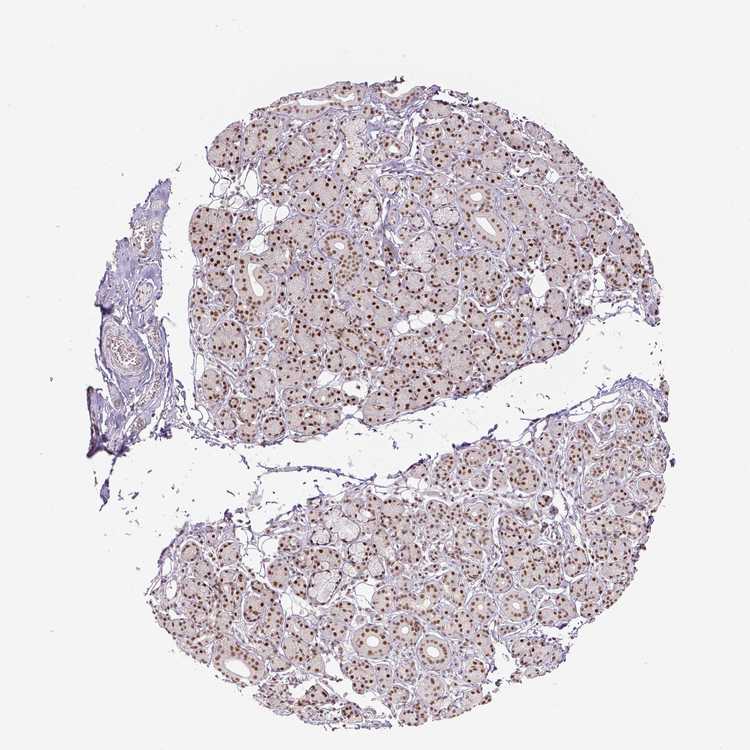

SALIVARY GLAND - Antibody stainingi

Antibody staining in the annotated cell types in the current human tissue is reported as not detected, low, medium, or high, based on conventional immunohistochemistry profiling in selected tissues. This score is based on the combination of the staining intensity and fraction of stained cells.

Each image is clickable and will lead to virtual microscopy that enables deeper exploration of all samples and also displays staining intensity scores, fraction scores and subcellular localization as well as patient and tissue information for each sample.

Antibody HPA029773Antibody CAB004390Antibody CAB072859Antibody CAB072860

Glandular cells MediumHighHighHigh